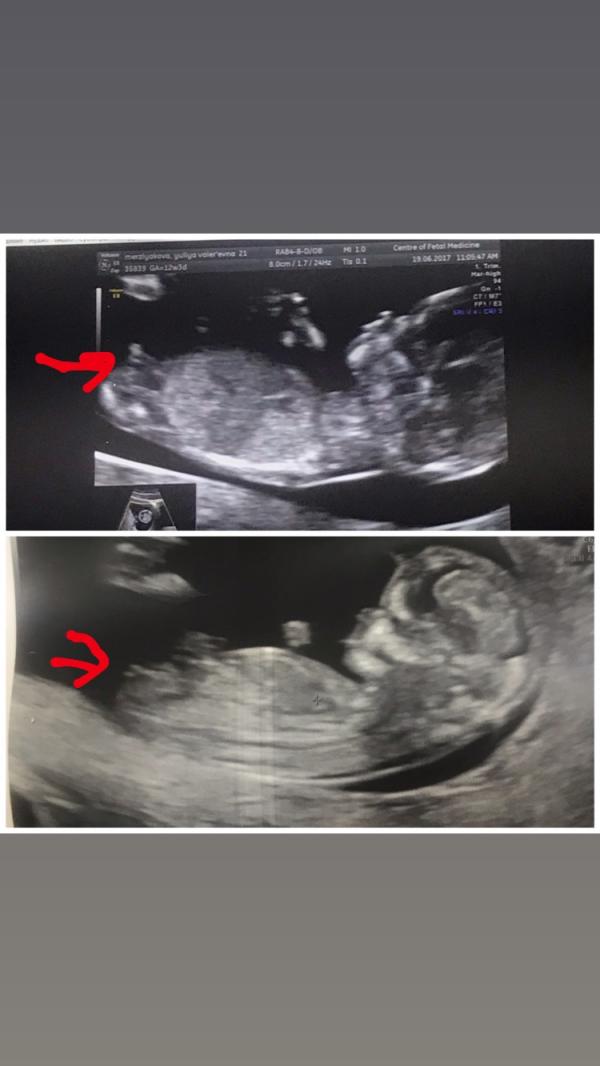

Как известно, к моменту первого скрининга половые органы плода ещё не сформированы, и опытные узисты делают свои предположения исходя из угла отростка, так вот нашла я фото-пример в интернете и сравнила с узи моих детей (фото 2): сверху сын, снизу дочь 🤪 Ну и, собственно, в 17 недель нам подтвердили девочку 😁 Любопытство крайней степени.